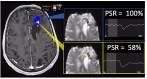

In the follow-up treatment of high-grade gliomas (HGGs), differentiating true tumor progression from treatment-related effects, such as pseudoprogression and radiation necrosis, presents an ongoing clinical challenge. Conventional MRI with and without intravenous contrast serves as the clinical benchmark for the posttreatment surveillance imaging of HGG. However, many advanced imaging techniques have shown promise in helping better delineate the findings in indeterminate scenarios, as posttreatment effects can often mimic true tumor progression on conventional imaging. These challenges are further confounded by the histologic admixture that can commonly occur between tumor growth and treatment-related effects within the posttreatment bed. This review discusses the current practices in the surveillance imaging of HGG and the role of advanced imaging techniques, including perfusion MRI and metabolic MRI.